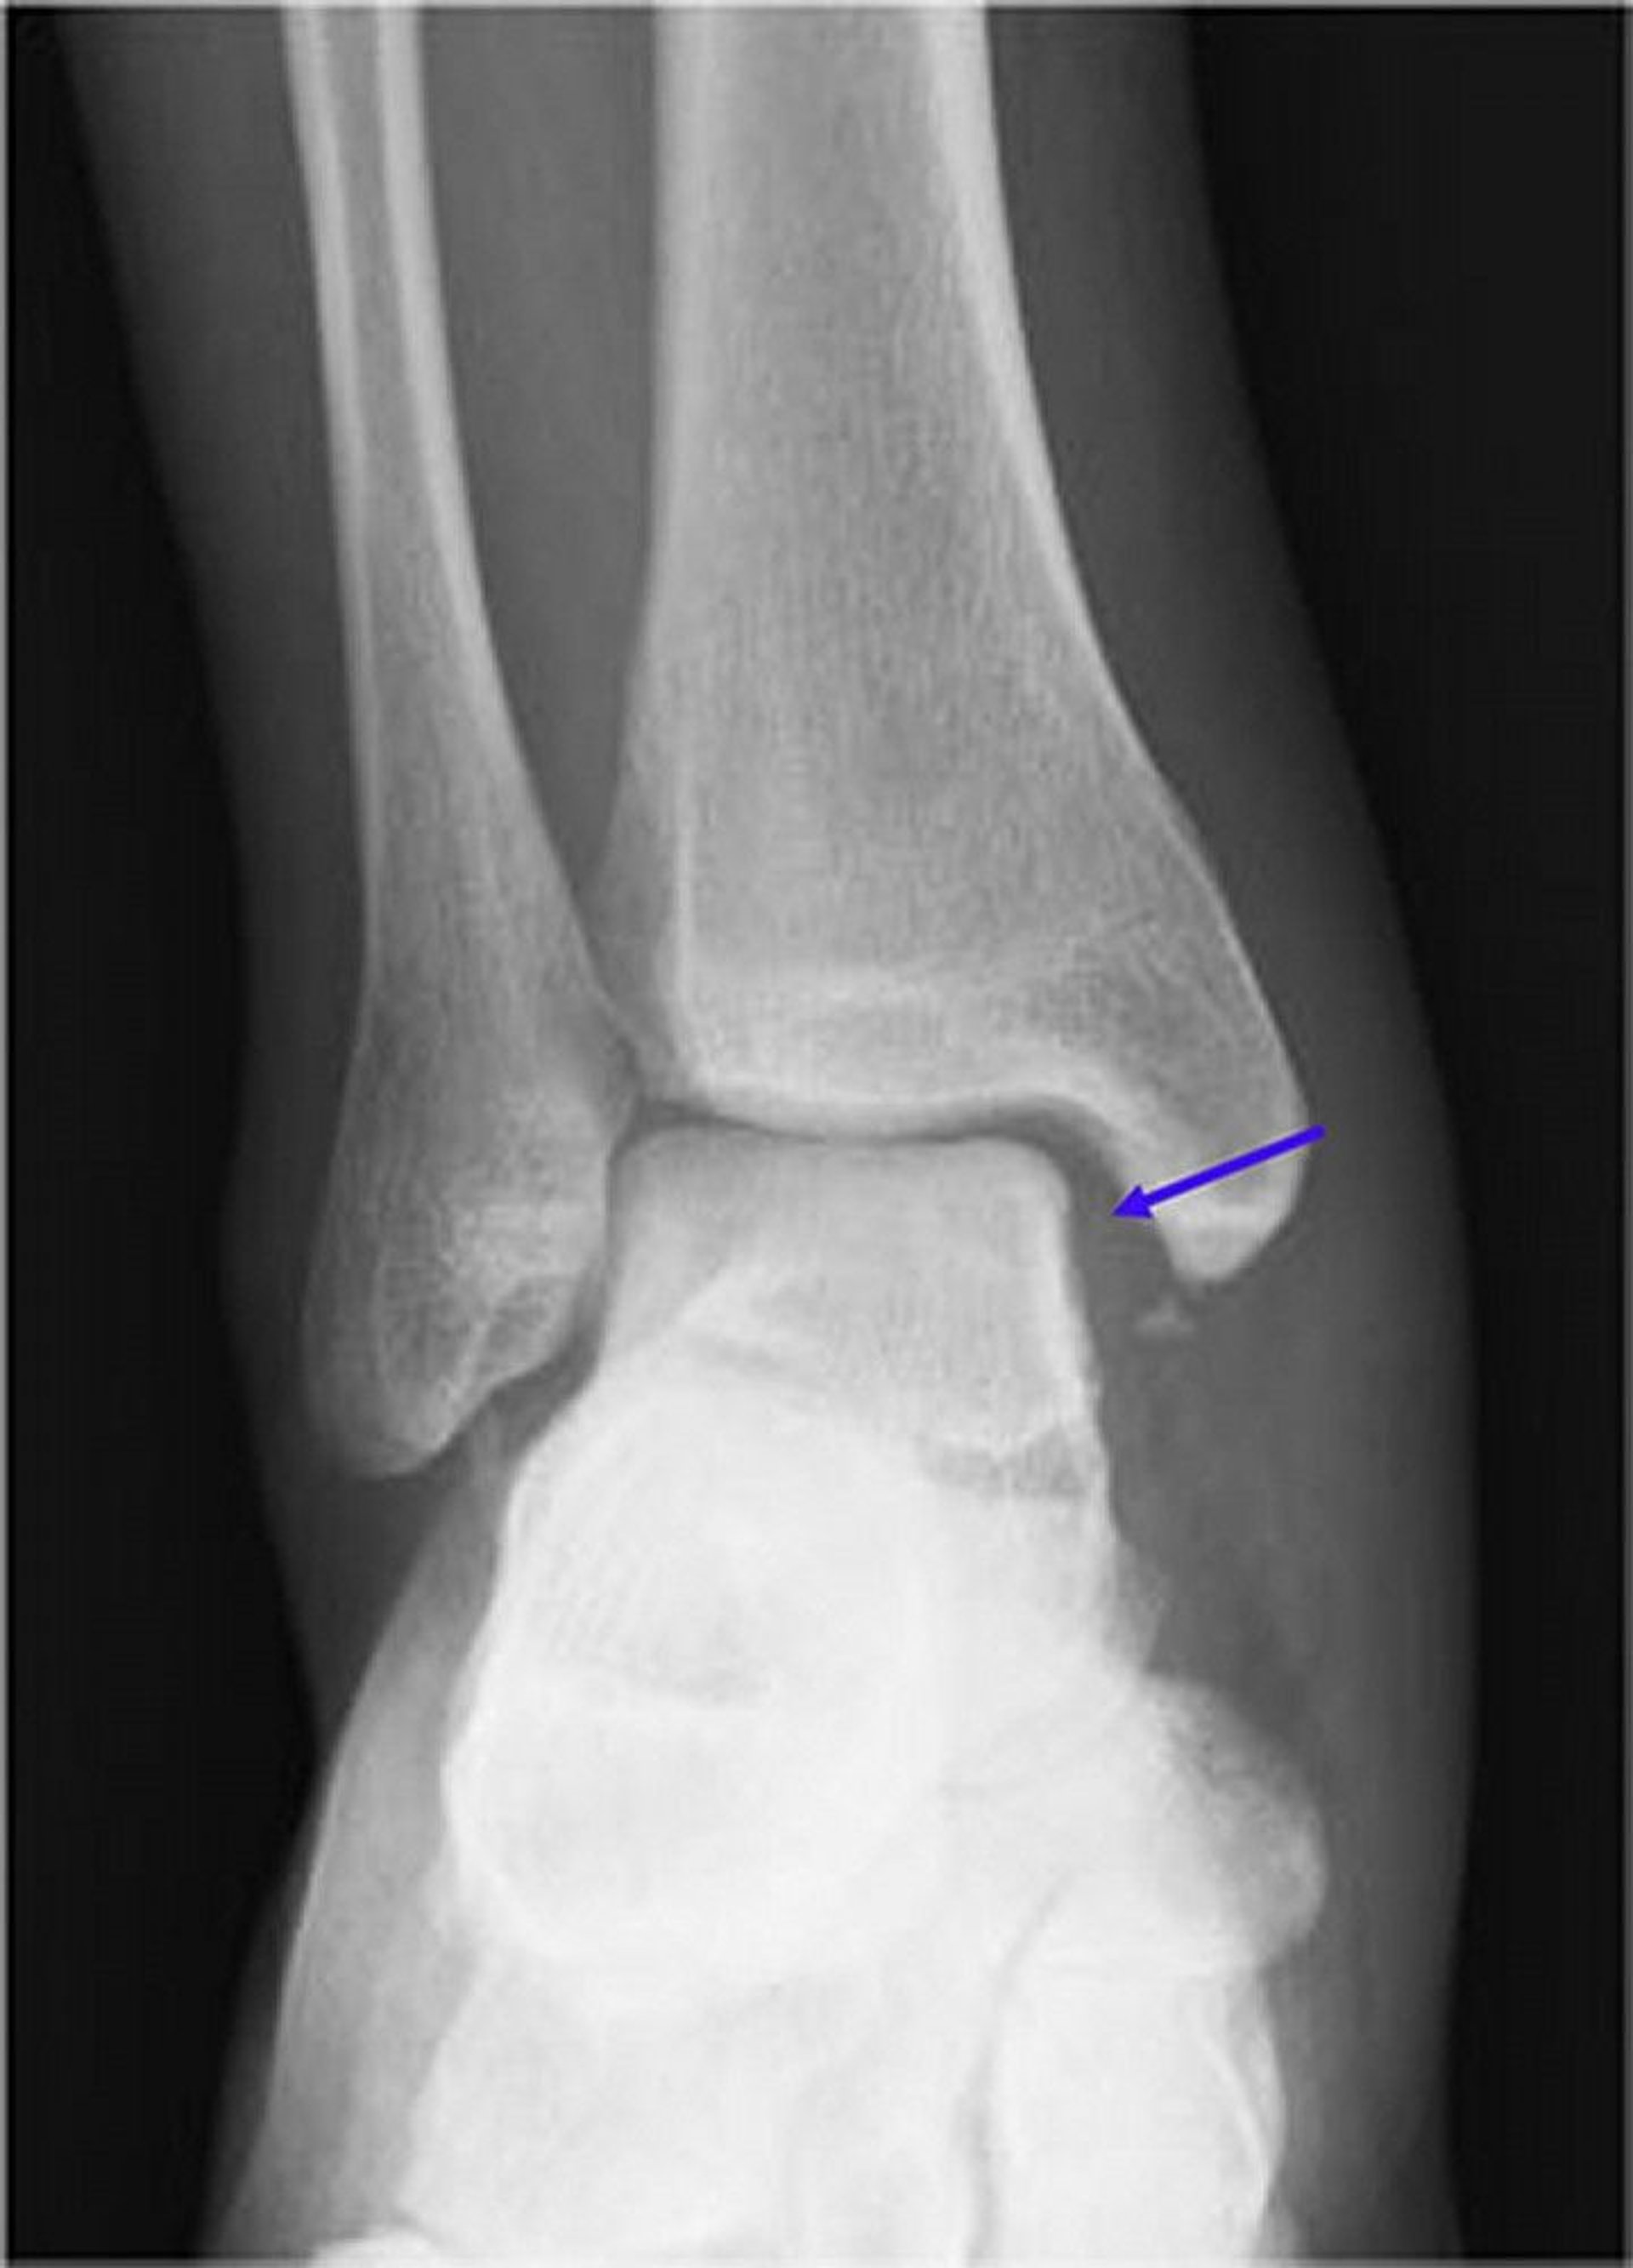

This radiograph shows a disruption (widening) of the medial mortise joint (blue arrow). Normally, the space of the mortise joint should be symmetric around the talus. With a concomitant proximal fibular fracture, this is known as a Maisonneuve fracture.

Image courtesy of Danielle Campagne, MD.